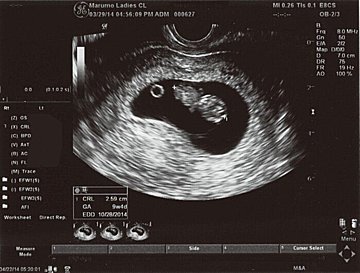

画像中央の+と+の間が赤ちゃんで、上の丸い頭のようなものが赤ちゃんに栄養を送る袋(卵黄嚢)だと教えてもらいました。家に帰って、気になっていたエコー写真の記号の意味を調べてみたら以下の通りだと分かり、まだ頭からお尻まで13.4mmなのだとその小ささに驚きました。

GS 胎嚢(たいのう)=胎嚢のサイズ

BPD 児頭大横径(じとうだいおうけい)=赤ちゃんの頭の幅

CRL 頭殿長(とうでんちょう)=赤ちゃんの頭からお尻までの長さ